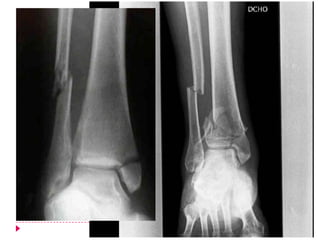

   Transindesmotica o tipo B

   El peroné tiene fractura oblicua ascendente

   Se puede acompañar de fractura transversa del maléolo medial

   El mecanismo es por eversión

   El trazo de fractura inicia a nivel del plafón tibial extendiéndose

proximalmente de manera oblicua o espiroidéa

   El 50% de éstas son quirúrgicas

   Suprasindesmotica o tipo C

  El peroné se encuentra fracturado por arriba de la sindesmosis

 El maléolo medial presenta fractura transversa

 Mecanismo es por abducción-rotación

 Si compromete sindesmosis y membrana interósea compromete

la estabilidad del tobillo

 Si no compromete la estabilidad

o la mortaja, puede realizarse un

tratamiento conservador

 Yeso corto